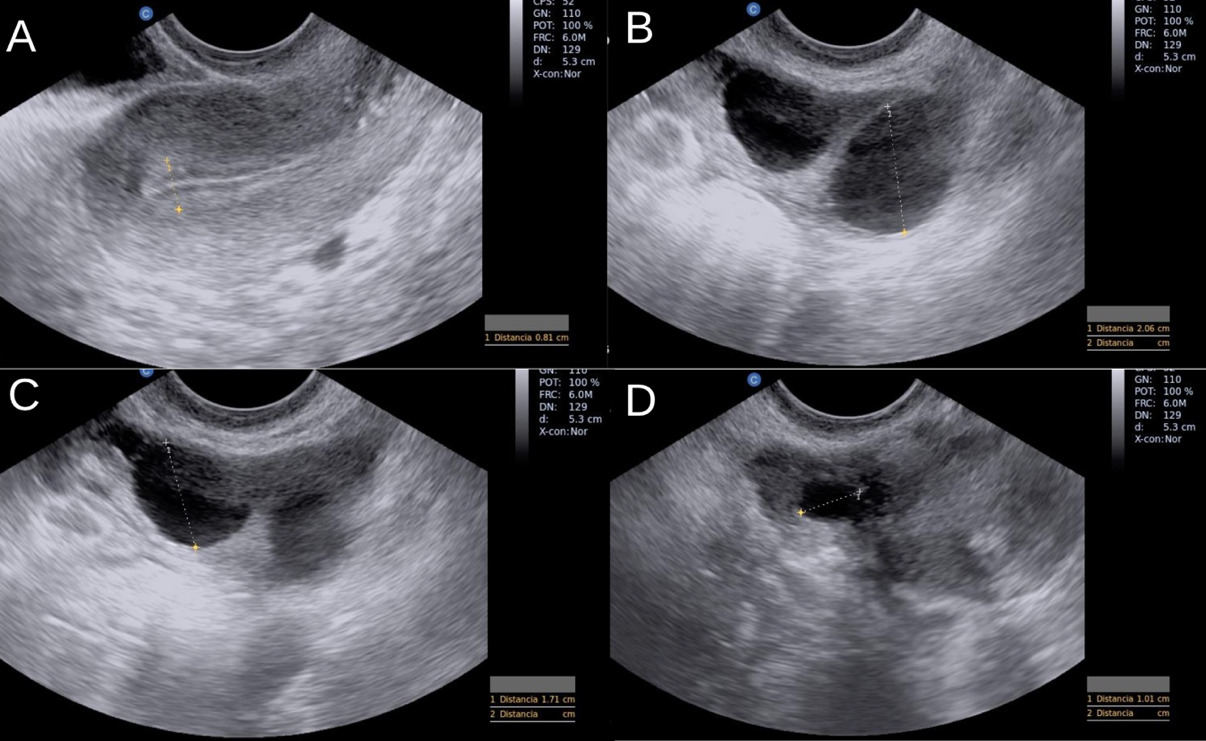

We decide on high-complexity treatment (IVF/ICSI) to increase the chances of pregnancy, using menotropins 300 IU every 24 hours plus dihydrogesterone 30mg orally, as well as the use of testosterone 50 mg transdermal every 24 hours to improve the ovarian response starting from 3rd day of the menstrual cycle. An endocavitary ultrasound was performed on day 11 of the cycle (IMAGE 1). Subsequently, a serum sample of estradiol and progesterone was taken, resulting in 1010.14 pg/ml and 0.63 ng/ml, respectively. Final oocyte maturation was performed with hCG 10,000 IU. Oocyte capture is carried out at 34 hours after day 13 of the cycle, obtaining 4 oocytes being 2 MII; due to the poor response, vitrification of the oocytes obtained was proposed (IMAGE 2), and carrying out from another cycle of ovarian stimulation controlled to obtain more mature oocytes and perform ICSI.